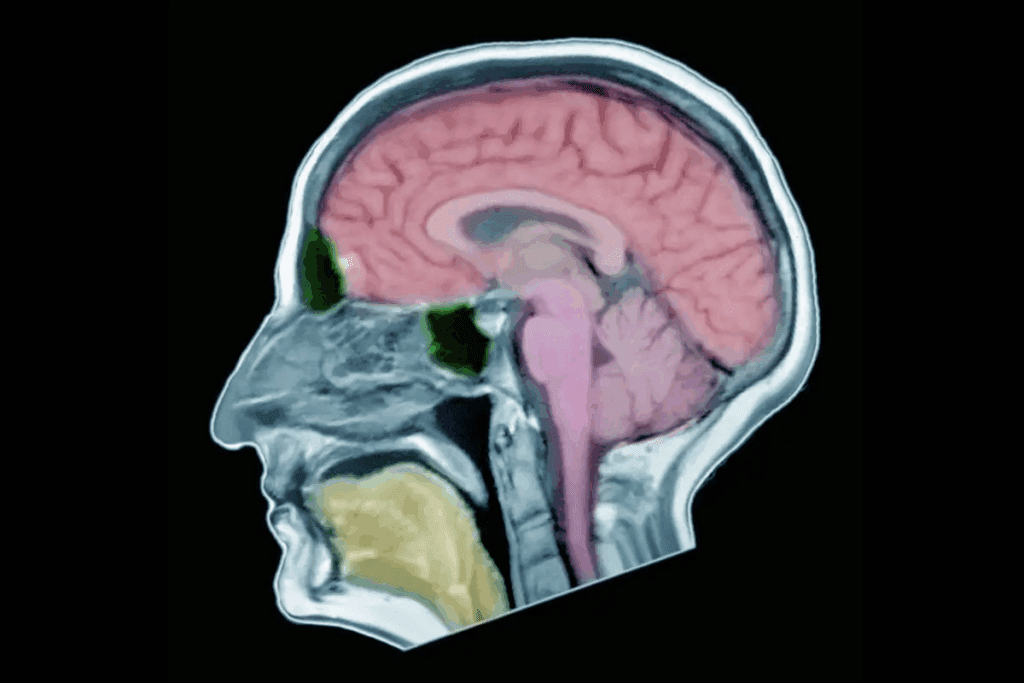

Anatomy and Location of the Pituitary Gland

The pituitary gland sits in a bony space called the sella turcica, at the brain’s base. It’s connected to the hypothalamus by a stalk called the infundibulum. It has two main parts: the anterior and posterior pituitary.